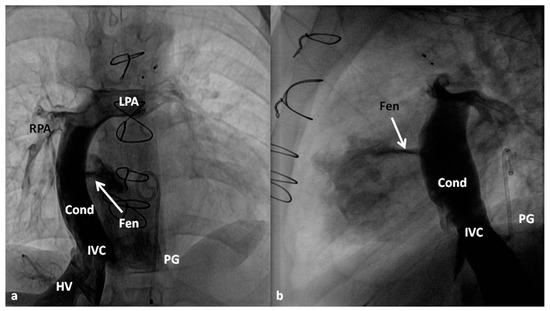

4.2.3. Stage IIIA

Between the ages of one and four years, usually one year after the bidirectional Glenn, Fontan completion is performed by redirecting the inferior vena caval flow into the PA by either a lateral tunnel [81] or an extra-cardiac non-valved conduit [76]. Extra-cardiac conduit with fenestration (Figure 10) is preferred by most surgeons. Cardiac catheterization and selective cine-angiography is usually performed prior to this surgery to evaluate pulmonary artery anatomy and pressures, trans-pulmonary gradient, pulmonary vascular resistance (PVR), and LV end-diastolic pressure to ensure their normalcy prior to proceeding with Fontan completion. Some centers use magnetic resonance imaging (MRI) for evaluation instead of angiography. During this catheterization, significant collateral vessels, if present, are trans-catheter occluded by most cardiologists.

4.2.4. Stage IIIB

The fenestration is closed by trans-catheter device implantation (Figure 11) six months to one year after stage IIIA. Occlusion of the fenestration is not necessary in all patients, although the author recommends closure to prevent arterial desaturation and paradoxical embolism.